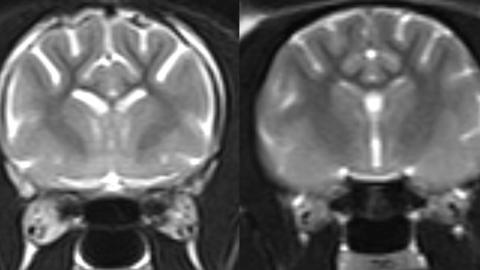

Experts at the University of Edinburgh carried out a post-mortem brain examination on 25 cats which had symptoms of dementia in life, including confusion, sleep disruption and an increase in vocalisation.

They found a build-up of amyloid-beta, a toxic protein and one of the defining features of Alzheimer's disease.